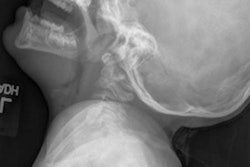

The U.S. Food and Drug Administration (FDA) published a final guidance on November 28 regarding pediatric x-rays, recommending dose reductions in new x-ray devices.

The guidance, Pediatric Information for X-ray Imaging Device Premarket Notifications, recommends manufacturers include dose reduction features in their equipment designs and pediatric resources when they develop and manufacture x-ray equipment. The FDA also suggests industry ensure the tools are straightforward to implement with clear, understandable instructions on how to optimize dose.